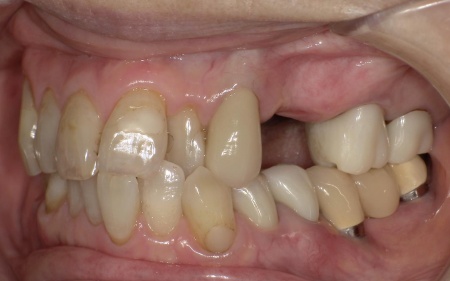

今回は審美性を考慮して、金属のバネではなく樹脂の留め具で固定する部分入れ歯「ノンクラスプデンチャー」を提案し、同意いただきました。

ノンクラスプデンチャーの留め具は歯茎に近い色をしているため、目立ちにくいのが特徴です。

また、体調が回復した時点でインプラント治療へ移行する可能性もふまえ、ノンクラスプデンチャーは手術部位を圧迫しにくく、調整がしやすい設計で作製することになりました。

3ヶ月間の経過観察後、傷が治癒したことが確認できたため、ノンクラスプデンチャーを作製するための型取りを行いました。

また、噛み合わせの記録を取ったり、周囲の歯に馴染む色調の人工歯を選んだりなど、患者様によりぴったりと合う入れ歯に仕上げています。

約3週間後、完成した入れ歯を装着し、使用感や見た目に問題がないことを確認して、治療を終了しました。